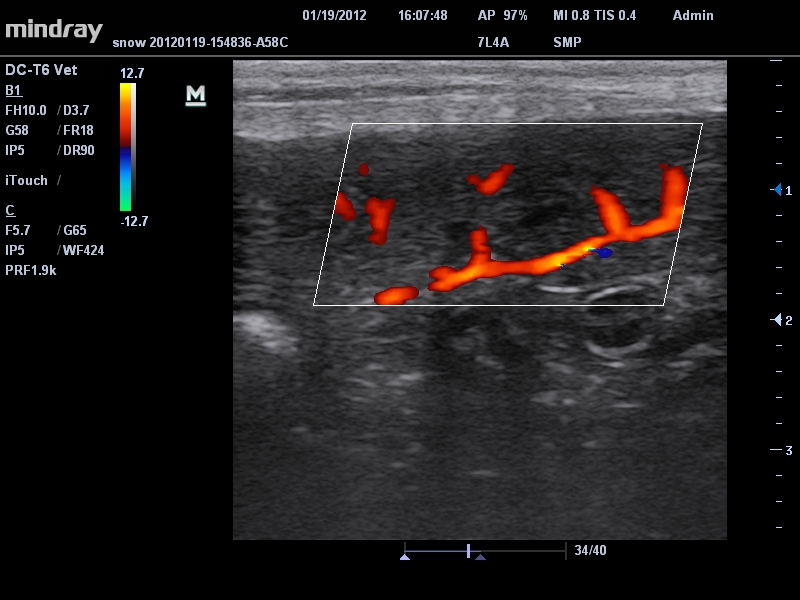

Mindray DC-T6

Ультразвуковая система Mindray DC-T6 – это инновационный аппарат для проведения высокого уровня диагностики с качественной визуализацией и широким спектром применения. Платформа рекомендована для использования в коммерчески многопрофильных медицинских учреждениях и государственных лечебных клиниках.

Ветеринария:

Да

• Режимы сканирования: B/M/CFM/PDI/Направленный PDI/PW, HPRF, Тканевая гармоника, М- и цветной М-режим.

• Линейный ультразвуковой датчик Mindray 7L4A